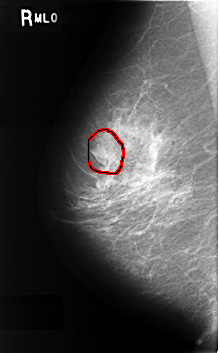

C_0338_1.RIGHT_MLO

FILE: C_0338_1.RIGHT_MLO.OVERLAY

TOTAL_ABNORMALITIES 1

ABNORMALITY 1

LESION_TYPE MASS SHAPE OVAL MARGINS CIRCUMSCRIBED

ASSESSMENT 4

SUBTLETY 3

PATHOLOGY BENIGN

TOTAL_OUTLINES 1

BOUNDARY